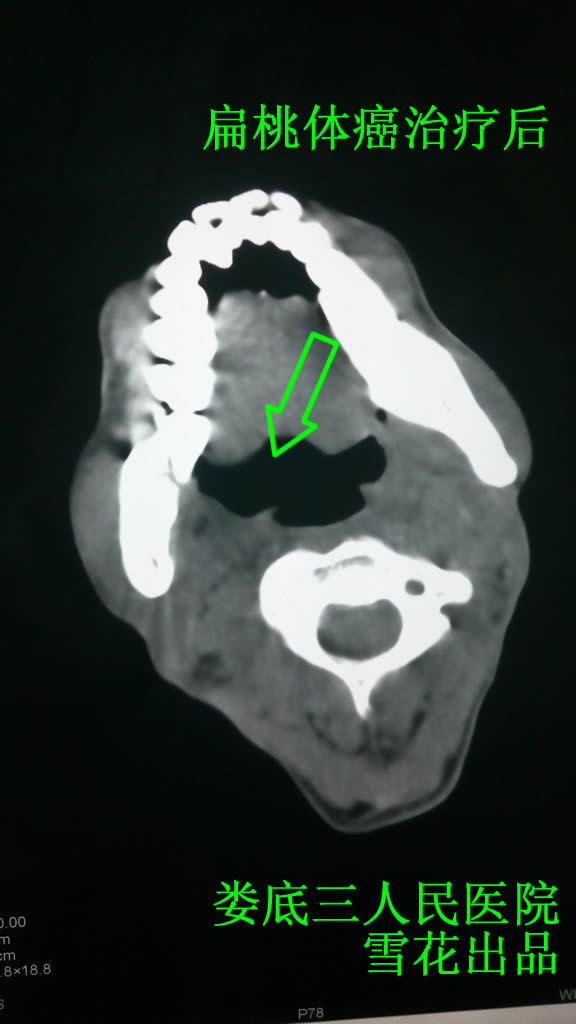

XX,男,42岁,20124月因“右侧咽部疼痛1年”到新化县人民医院检查,考虑扁桃体癌,到湖南省肿瘤医院行扁桃体穿刺活检,确诊为高-中分化鳞癌,为求治疗来我院。查口咽CT示右侧扁桃体体积增大,周围脂肪间隙消失,右侧口腔变小(见图一)。入院给予放疗,原发灶给予70Gy/35/47天,下颈前切野给予60 Gy/30/40天,放疗10次后患者咽干疼痛,开始出现口腔溃疡,进食疼痛,给予中药口服,当时查舌象为瘦红舌,少苔,脉细涩,考虑为阴虚火旺,并有体内淤血,给予中药一贯煎加减方口服,具体如下:

口服7剂后患者咽干疼痛好转,未再出现新的口腔溃疡,坚持口服中药,直到放疗结束患者无明显放疗反应。之后行2周期化疗,均给予“紫衫醇210mg d1 DDP 40mg d1-3,期间坚持口服中药(方同上),每口服中药2周,休息1周,患者无明显化疗反应,复查口咽CT未见明显异常(见图二),出院时建议患者再化疗2周期巩固疗效,嘱咐患者坚持口服中药,坚持张口练习及颈部转动练习防止局部组织纤维化。出院后患者拒绝继续化疗,间断口服中药(方同上),现已追踪回访2年,未见复发及转移。